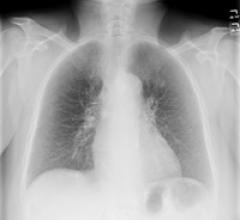

April 20, 2011 – A new study published in Radiology has demonstrated that using a bone suppression application with chest X-rays significantly increased the detection of lung nodules proven to be primary lung cancer. The study used Riverain Medical’s SoftView system.

July 20, 2010 – Siemens recently announced it is enhancing its digital radiography (DR) product with new software that takes existing chest X-rays and suppresses the ribs and clavicles to improve visibility of soft tissue structures of the lungs.